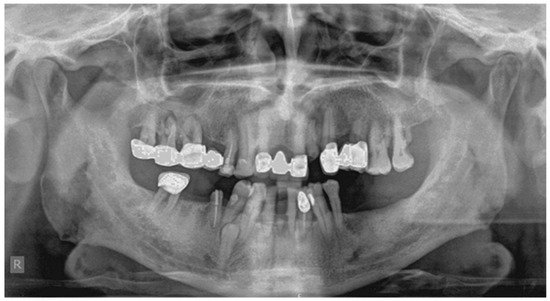

2.2. Case 2

Case 2 Presentation